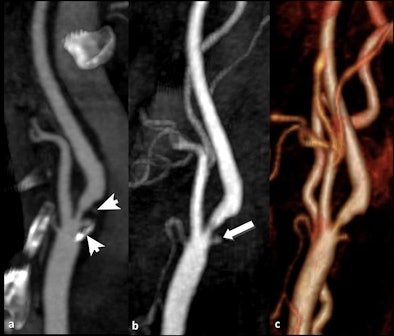

![]() |

| Patient with transient ischemic attack. A: CT angiography depicted a large plaque involving the internal carotid artery characterized by a proximal calcified component and a distal fibrolipidic portion (arrows); first-pass MRI (B) identified a small and deep ulceration of the plaque surface that was partially hidden by calcifications in CT (arrow). C: Volume-rendered reconstruction. (Provided by Prof. Carlo Catalano and Dr. Beatrice Cavallo Marincola) |